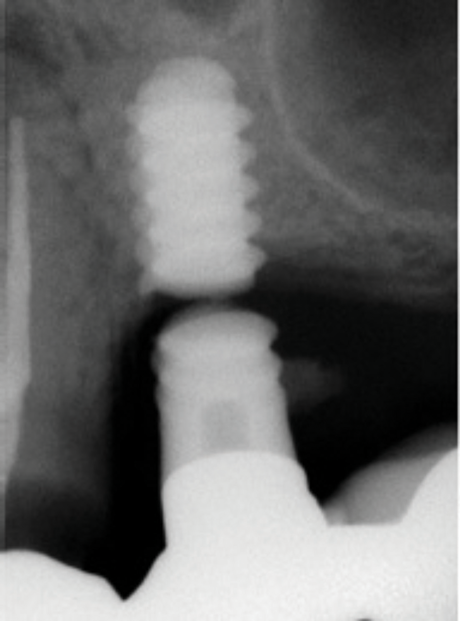

(4.) A failed implant that underwent mechanical overloading leading to fracture of the coronal portion adjacent to the implant-abutment connection.

Figure 4